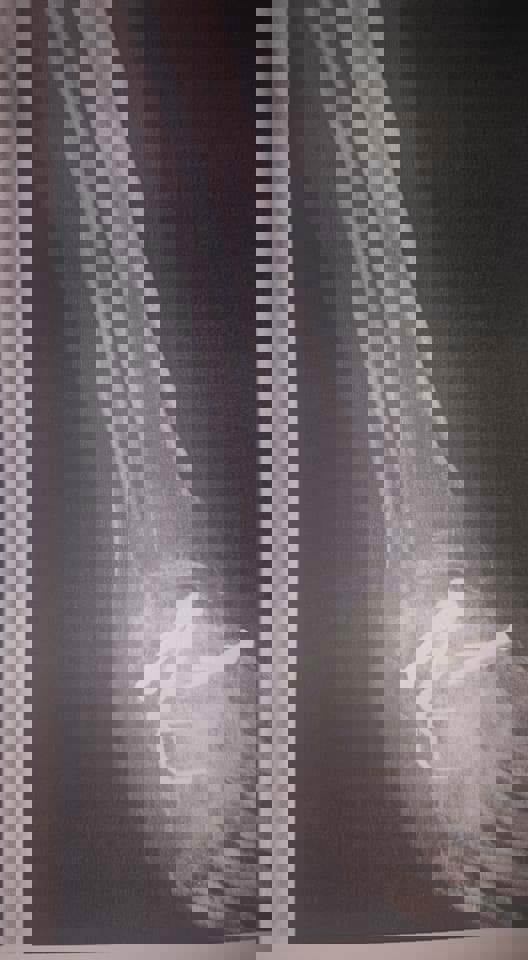

William is a devoted father to our two boys, and despite the challenges of his condition, he has always put our family first. From the very beginning, his life has been a constant battle born with Clubfoot on both feet, he spent his infancy in casts, wore special braces until he was five, and underwent countless surgeries to try to correct his feet. Even as a young child, he endured pain that most adults could not imagine.

In 2021, William received devastating news from his doctors: he might lose his ability to walk within a year. Miraculously, he defied the odds and continued walking for two more years—but eventually, at the age of 33, he lost the ability to walk entirely. Today, at 35, he relies on a wheelchair and lives in...